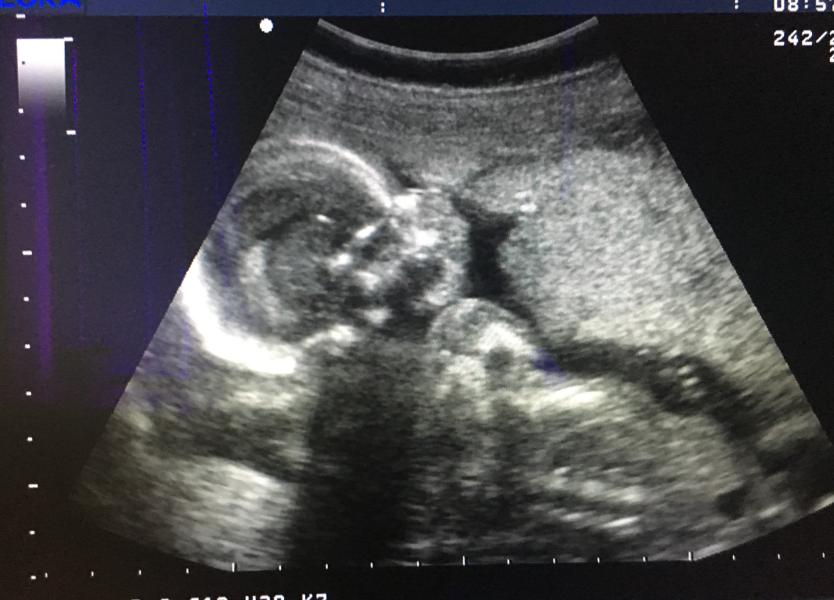

Сегодня была на втором скрининге 💙

Первые слова врача "ой, какой мальчик")) в глубине души закрадывались сомнения, что в 13 недель могли и неправильно увидеть пол) но нет😁 сынуля демонстрировал, то, что он именно сынуля во всей красе) поворачивался к датчику первичным половым признаком😁 это все очень мило, но УЗИ нужно будет переделывать, потому что не все смогли разглядеть🤷🏻♀️

Не знаю почему, действительно ли сын вредничал, либо аппарат не оч, либо врач (делала УЗИ не мой гинеколог)) это останется...